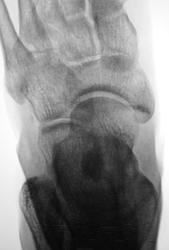

Травма.  Пациент направлен на рентгенографию стопы

P.S. похоже на костный островок

Не заметила ничего травматического...

Участок склероза или остеопойкилия.